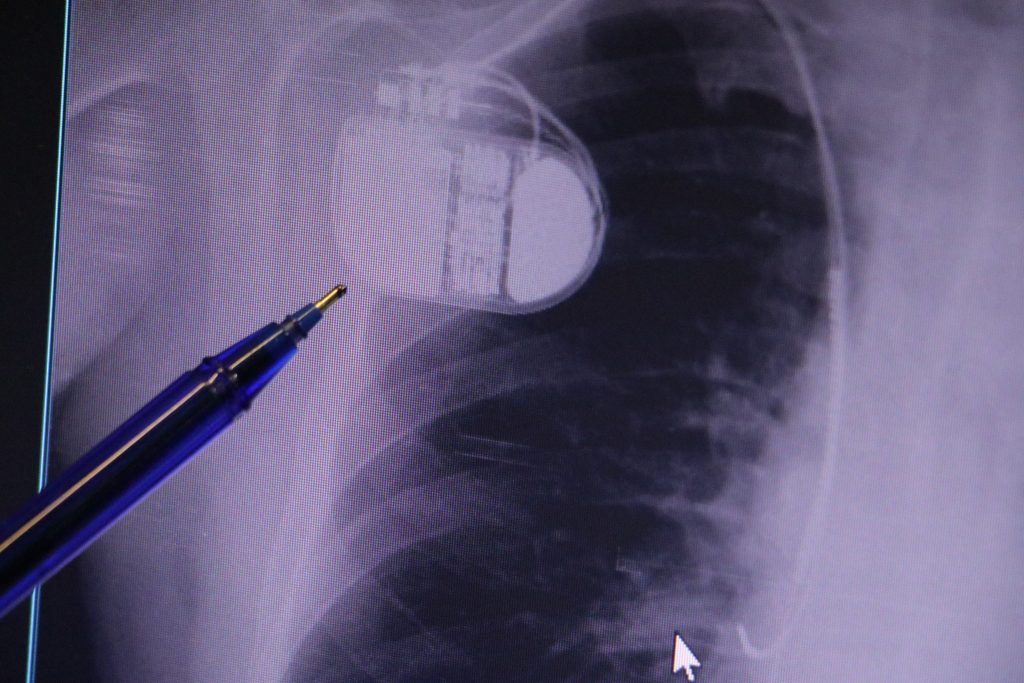

“Her öksürük basit bir soğuk algınlığı değildir. Zatürre, erken tanı konulmadığında ölümcül seyredebilen ciddi bir akciğer enfeksiyonudur. Özellikle çocuklarda, 65 yaş üzeri bireylerde, kronik kalp, böbrek ve akciğer hastalığı bulunanlarda ağır seyredebilir. Bu nedenle belirtiler başladığında vakit kaybetmeden bir uzmana başvurmak gerekir”

“Hastalığın en yaygın belirtileri yüksek ateş, öksürük, balgam, göğüs ağrısı, nefes darlığı ve halsizlik, erken tanı tedavinin başarısını büyük ölçüde arttırıyor. Zatürreye karşı en etkili korunma yönteminin zatürre (pnömokok) ve grip aşısı vurdurmak. Aşı, hastalığın hem görülme sıklığını hem de ölüm oranlarını ciddi ölçüde azaltır. Özellikle risk grubundaki bireylerin her yıl düzenli olarak aşı yaptırması hayati önem taşır. Ayrıca bağışıklık sistemini güçlendirmek için dengeli beslenme, hijyen kurallarına dikkat edilmesi, sigara ve alkol kullanımının bırakılması lazım, Zatürre tedavi edilebilir bir hastalıktır, ancak ihmale gelmez. Unutmayın, her öksürük masum değildir”